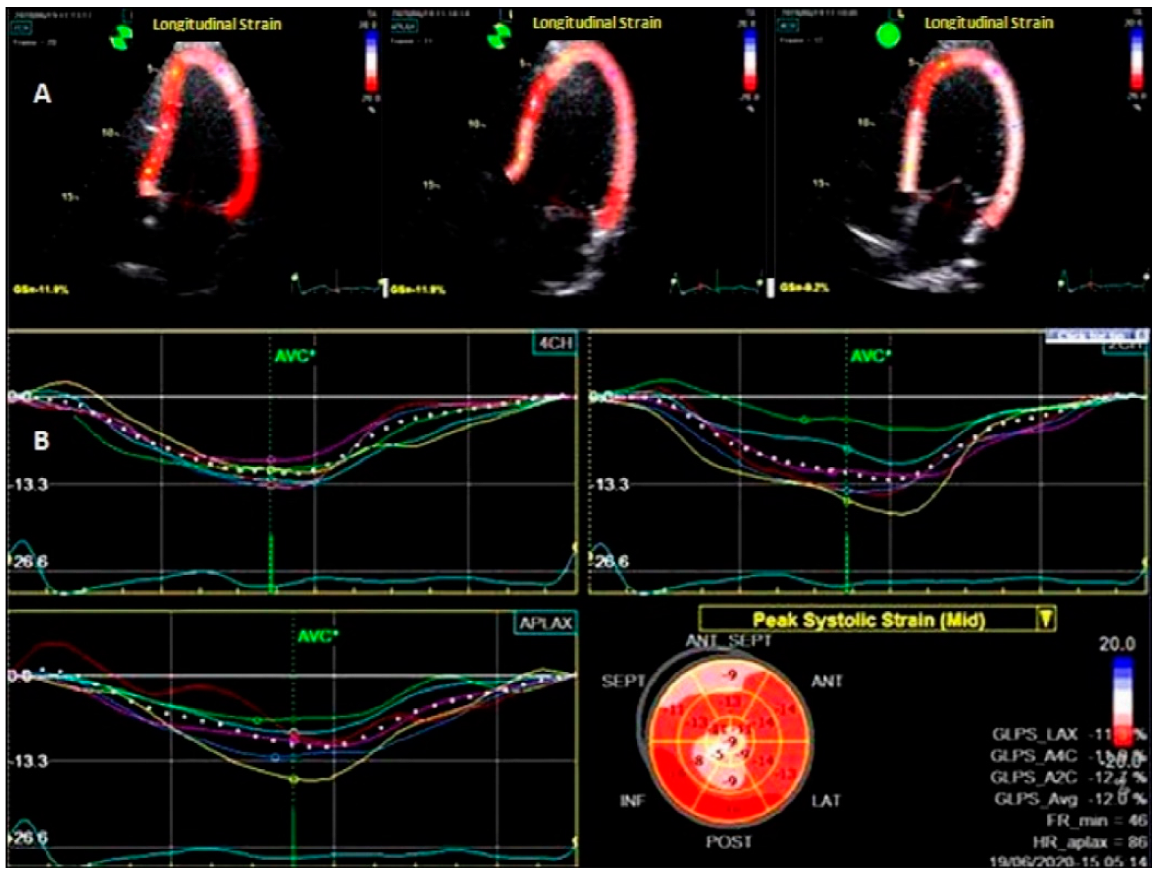

2.6.2. Two Dimensional-Speckle Tracking Echocardiography (2D-STE)

| ILS(%) | −13.1 (12.4, 14.00) | −12.3 (11.6, 12.8) | −12.9 (12.2, 13.8) | <0.0001 |

| ILSR (s−1) | −0.76 (0.70, 0.80) | −0.74 (0.69, 0.80) | −0.74 (0.69, 0.80) | 0.0004 |